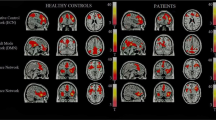

We found support for both convergent and divergent regions when conducting a contrast analysis of the two individual meta-analyses (PCC activation versus PCC deactivation) (Table 3 and Fig. 2). Generally, the meta-analytic functional pattern related to PCC co-activation was more extensive compared to the functional pattern of PCC co-deactivation. Areas of convergence between maps of co-activation and co-deactivation of the PCC include the left medial frontal gyrus, left midcingulate gyrus, left amygdala, and left anterior cingulate. These structures may be associated with mechanisms for increased and decreased concomitant co-activation or co-deactivation with the PCC.

Quantitative contrast analysis

We found support for convergent and divergent regions of co-activation and co-deactivation when conducting contrast analyses. We conducted four contrast analyses: dPCC co-activation versus dPCC co-deactivation, vPCC co-activation versus vPCC co-deactivation, dPCC co-activation versus vPCC co-activation, dPCC co-deactivation versus vPCC co-deactivation (Table 7, Fig. 3). Regions of convergence for dPCC co-activation and dPCC co-deactivation included bilateral midcingulate gyri and the right posterior cingulate. For the vPCC co-activation and co-deactivation contrast, regions of convergence included bilateral precuneus and the left midcingulate gyrus. The dPCC co-activation and vPCC co-activation contrast yielded regions of convergence including the left medial frontal gyrus and the left posterior cingulate. For the dPCC co-deactivations versus vPCC co-deactivations contrasts, regions of convergence included the right midcingulate and posterior cingulate gyri. Given the low number of deactivation papers, the following results should be interpreted with caution. In particular, warning messages appeared stating it was unlikely to have enough statistical power to show significant differences for two of the four contrasts, dPCC co-activation versus dPCC co-deactivation and dPCC co-deactivation versus vPCC co-deactivation.

d(v)PCC Co-activation > d(v)PCC Co-deactivation, d(v)PCC Co-(de)activation > v(d)PCC Co-(de)activation

The contrast of dPCC co-activation versus dPCC co-deactivation did not yield any significant regions of divergence. Similarly, the contrast for vPCC co-activation versus vPCC co-deactivation did not yield significant regions of divergence. In contrasting dPCC co-activation with vPCC co-activation, the right posterior cingulate (BA23) and left inferior parietal lobule emerged as regions uniquely co-activated with the dPCC and the right posterior cingulate (BA 31) and right precuneus emerged as regions uniquely co-activated with the vPCC. In contrasting dPCC co-deactivation with vPCC co-deactivation, the left posterior cingulate and left midcingulate gyrus were shown to co-deactivate uniquely with the dPCC. No regions emerged as uniquely co-deactivated with the vPCC.

Resting state functional connectivity

Resting state functional connectivity analyses using the PCC as the seed resulted in widespread whole-brain activation. Despite demonstrating a similar pattern of connectivity to the activation-based MACM, a few notable exceptions emerged (Figs. 4, 5). Convergent patterns of resting state functional connectivity with co-activation were identified with the anterior cingulate, medial frontal gyrus, left parahippocampus, left culmen, portions of the left and right thalamus, the left middle/superior temporal gyri, and the left inferior parietal lobe (please see Supplemental Information for a full table of local maxima). Resting state connectivity also demonstrated differential patterns of functional connectivity in bilateral superior parietal regions, as well as right inferior parietal regions and superior temporal regions. We also noted bilateral pulvinar and superior frontal gyri connectivity specific to resting state data. In addition, similar to the pattern displayed when comparing co-activation with co-deactivation, we saw co-activation in sub-cortical regions such as the bilateral claustrum, right putamen, right medial globus pallidus, and left thalamus as well as bilateral midcingulate gyri extending from supplementary to pre-supplementary motor cortices, compared to resting state connectivity.

Qualitative comparison of rs-fMRI and MACM activations for the PCC ROI. ALE maps were thresholded using pcluster-corrected < 0.05 (1000 permutations) and ppvoxel-level < 0.001. Rs-fMRI seed-to-voxel connectivity maps were thresholded at pFDR-corrected < 0.001 at the voxel-level and pFWE-corrected< 0.001 at the cluster-level (two-tailed)

Qualitative comparison of rs-fMRI and MACM deactivations for the PCC ROI. ALE maps were thresholded using pcluster-corrected < 0.05 (1000 permutations) and ppvoxel-level < 0.001. Rs-fMRI seed-to-voxel connectivity maps were thresholded at pFDR-corrected < 0.001 at the voxel-level and pFWE-corrected< 0.001 at the cluster-level (two-tailed)